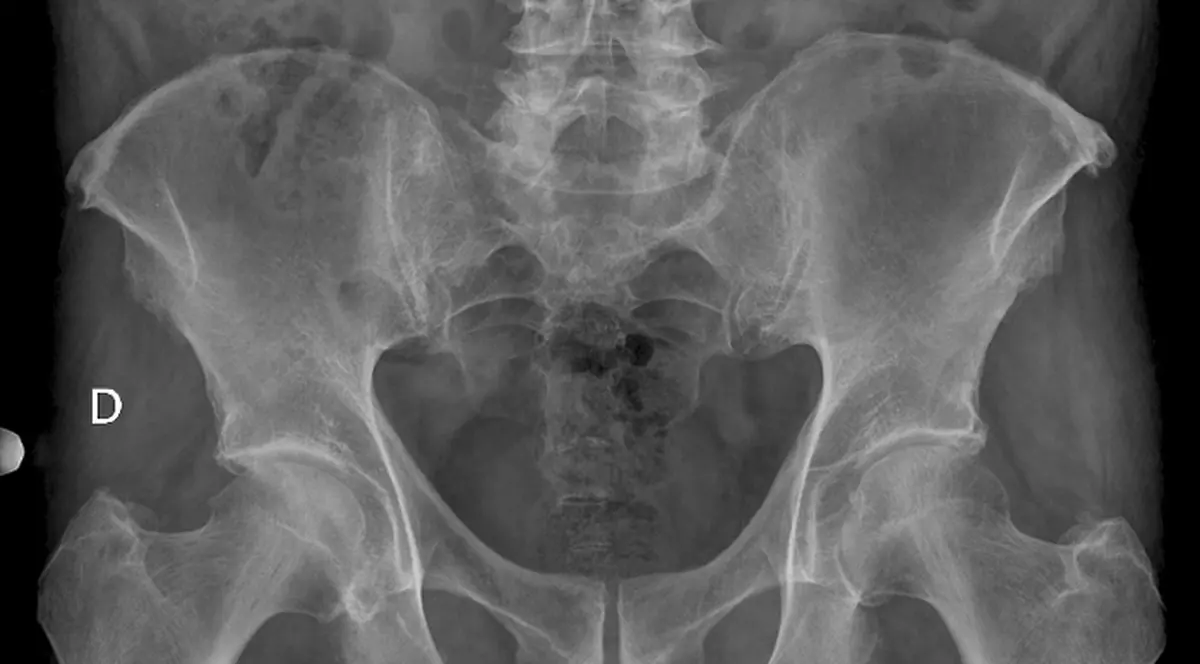

Duan Zhicai le-a povestit medicilor că a luptat pentru ţara sa în războiul contra Chinei, în anul 1943, ceea ce înseamnă că a stat cu obiectul străin în el timp de… 70 de ani. Bătrânul s-a arătat uluit de descoperirea medicilor şi a spus că nu avea idee că asta ar fi putut fi sursa durerilor lui.

Medicii au decis să nu-l opereze pe bătrânel pentru a-i scoate obiectul din pelvis, deoarece vârsta înaintată nu-i permite să treacă printr-o anestezie generală. „Glonţul nu-l pune viaţa în pericol, dar scoaterea lui da. Îi vom da pastile pentru ameliorarea durerilor, pentru că nu ne putem asuma riscul unei operaţii”, a mai spus purtatorul de cuvînt al spitalului.